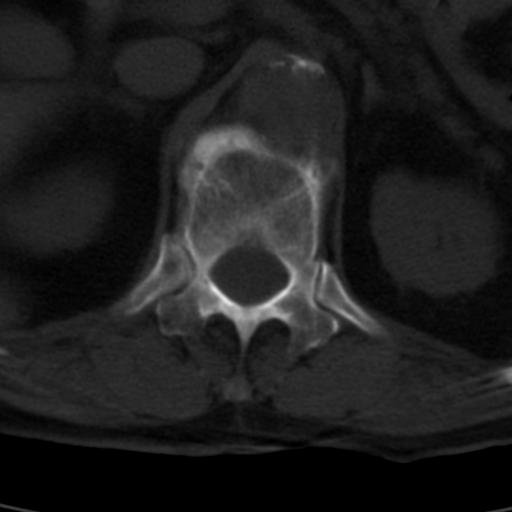

男性 82 主动脉夹层 请大家看看椎体是什么改变啊

腰椎退行性变,明显的骨赘形成,所指低密度灶为正常松质骨。